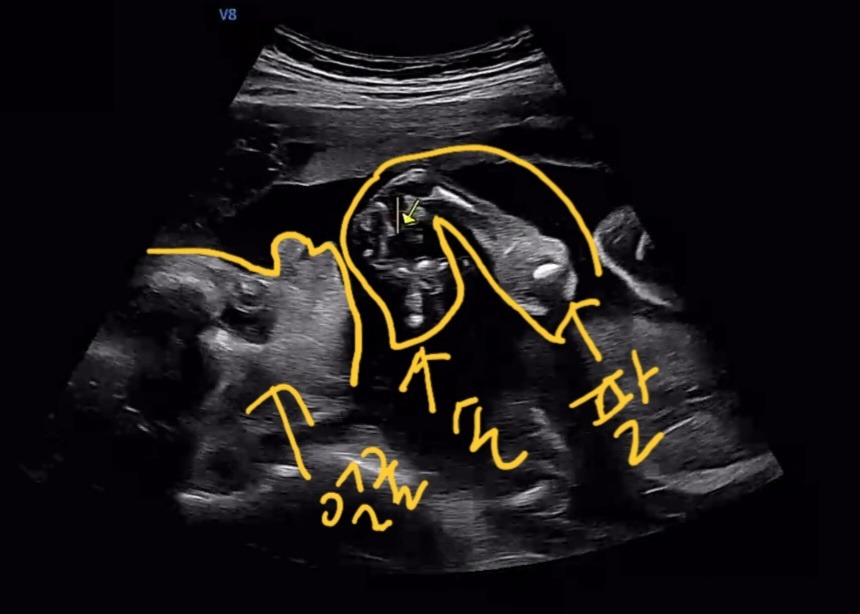

그리고 그날은 24주 차로 정밀 초음파 검사도 같이 했다.

까꿍이의 눈, 코, 입, 심장, 뇌, 장, 척추, 동맥 등 초음파로 확인할 수 있는 부분은 다 확인했다.

손과 발도 확인했는데, 까꿍이가 왼손을 턱에 괴고 있어서 손가락 개수 확인이 어려웠다.

손괴고.jpg 이런 식으로 있었다 ㅋㅋ 생각하는 아이?

왼발도 태반에 딱 붙이고 있어서 확인이 어려웠는데

왼손 왼발은 다음 입체 초음파 때 확인하자고 하셨다.